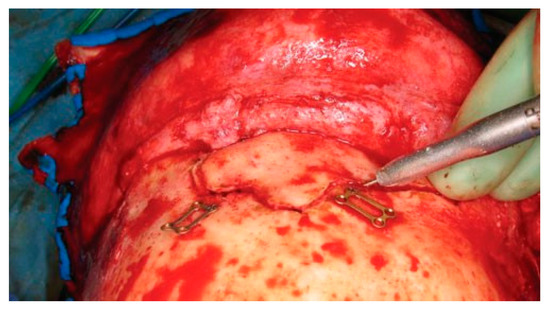

The patient gives consent after being informed of the risks of bleeding, infection, paresthesia, brain injury, CSF leak, meningitis, diplopia, visual loss, external deformity, and late mucocele formation. A coronal flap is used to expose the fracture as previously described. The full pericranial flap should be maintained to repair any CSF leak, dural defect, or obliteration of the sinus. After complete exposure, all anterior table bone frag- ments should be removed and kept moist. Placing the fragments atop a drawing of the fracture will help maintain the anatomic orientation of each segment prior to the repair. With fractures isolated to one side of the sinus, it is often necessary to perform a frontal sinus- otomy to remove the remainder of the anterior table bone. Localization of the sinusotomy cuts can be per- formed in several ways. Historically a ‘‘6-foot penny Caldwell’’ X-ray was used (i.e., anterior-posterior Cald- well X-ray with the patient placed 6 feet from the X-ray tube). However, current digital radiograph technology has made these images difficult to obtain. Intraoperative navigation is accurate but requires a specialized scan and navigation hardware. Alternatively, one tine of a bipolar cautery can be placed on each side of the anterior table. The internal tine is then used to ‘‘walk’’ around the periphery of the sinus, and the outer tine is used to mark an outline of the sinus using a bovie electrocautery (Figure 19). A final technique involves insertion of a light source into the sinus through a fracture line; this trans- illuminates the periphery of the sinus and guides the osteotomy.

Figure 19.

Intraoperative photo demonstrating the use of bayonet forceps to outline the periphery of the frontal sinus.

After the limits of the sinus have been defined, two microplates (1.0 to 1.3 mm) are preapplied with 3- to 4-mm screws, spanning the proposed osteotomy site. This allows the surgeon to accurately reapproximate the bone fragments despite the fact that a bone defect (or kerf) will be formed with the osteotomy. Although a sagittal saw can be used to perform the sinusotomy, the author prefers a Midas Rex drill (Medtronic, Fort Worth, TX) with a B-1 bit, which has both drilling and side-cutting capabilities. The surgeon should ini- tially use the bit to drill ‘‘postage stamp’’ perforations around the periphery of the sinus. The drill must be angled toward the sinus cavity to avoid intracranial penetration and injury. The side-cutting capability of the bit can then be used to join the perforations and complete the osteotomy (Figure 20). Care should be taken to avoid obliteration of the predrilled miniplate holes while performing the osteotomy. Particular attention should be paid to osteotomize the lateral orbital rims and the glabella without injury to the supraorbital/supratrochlear neurovascular pedicles. These osteoto- mies can be performed with a sharp 2- to 4-mm osteotome or the B-1 bit. A curved 4-mm osteotome is then inserted along the frontal osteotomy and used to break down any intersinus septations. Finally the ante- rior table is outfractured and hinged anteriorly.

Figure 20.

Intraoperative photo of a frontal sinusotomy. The drill should be held at an angle to avoid entry into the intracranial cavity. Note that the plates used for fixation of the anterior table bone at the end of the procedure have been preapplied prior to the sinusotomy.